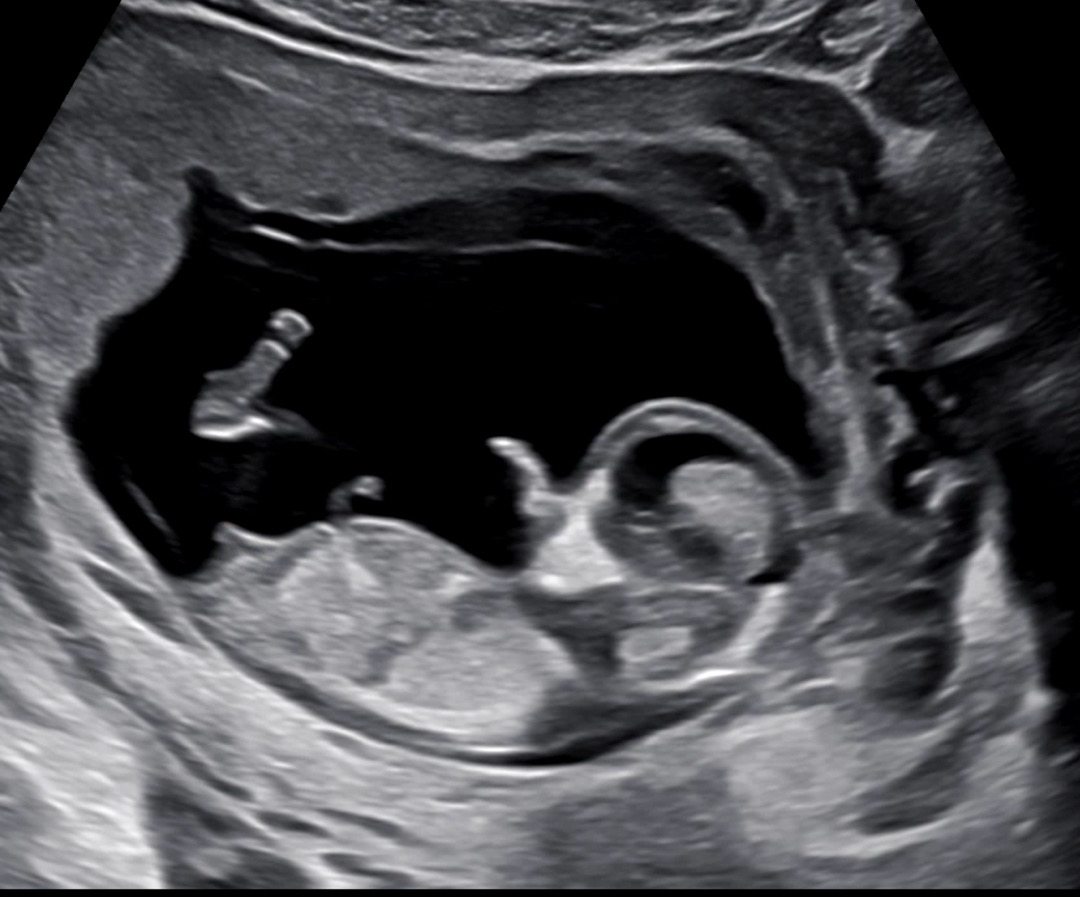

12주 4일 각도법 부탁드려요/결과 나오면 공유할게용

아들일까요 딸일까요 고수님들 봐주세용 후기 귀여운 여아였습니다 ㅎㅎ